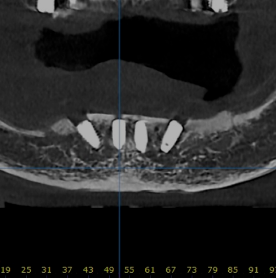

ALL IMPLANT VS FULLARCH

전체임플란트 vs 풀아치

나에게 꼭 맞는 치료법은?

풀아치가 필요한 경우

틀니를 오래 사용하셨거나, 잇몸뼈가 전반적으로

많이 내려앉아 치아만 만들 경우

너무 깊이 보이는 분들에게 가장 이상적입니다.

전체 임플란트가 더 나은 경우

치아를 뺄 지 않아도 잇몸뼈가 충분히 남아있는 분들은

잇몸 뼈를 삭제할 필요 없이, 치아만 만드는

전체 임플란트가 더 적합할 수 있습니다.